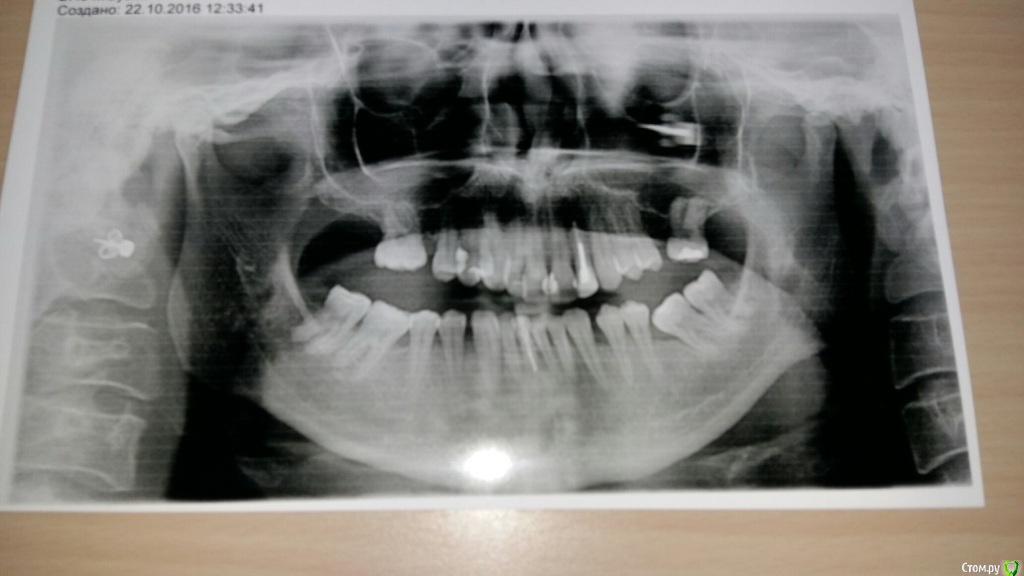

VVQW Опубликовано 25 октября, 2016 Поделиться Опубликовано 25 октября, 2016 (изменено) добрый день. Сложная ситуация. Более 10 лет назад ставили брекеты без анализов, диагностик, снимков и пр. Сейчас, что имееем, то и имеем. Большую проблему. Прикуса нет. Клиновидки из-за перегруза. Что можно сделать прошу совета и помощи. Обращалась за консультацией ко многим специалистам, мнения разнятся от слегка положительного, до просто критической ситуации. Последний профессор ортодонт вообще сказал - все вырвать и поставить протезы. УЖАС..... Может кто-нибудь из врачей даст совет... очень на Вас надеюсь. С уважением. Изменено 25 октября, 2016 пользователем VVQW Ссылка на комментарий

VVQW Опубликовано 6 декабря, 2016 Автор Поделиться Опубликовано 6 декабря, 2016 (изменено) Лечение скорее всего будет неким компромисом. Я правильно понимаю, 10 лет назад сняли брекеты?Брекеты были сняты более 10 лет назад. Ретейнеры не ставились. Верхние 6-ки по решению врача были убраны для задвигания зубов к заду, верхние 8-ки - не выросли. Нижние 6-ки - удалены в подростковом возрасте, до 14 лет. http://s019.radikal.ru/i641/1612/eb/3498e6cec3f8.jpg http://s018.radikal.ru/i518/1612/73/739600b6d2d1.jpg http://s011.radikal.ru/i318/1612/73/443e1513aaf8.jpg http://s017.radikal.ru/i403/1612/86/73e0dfe4ca62.jpg http://s018.radikal.ru/i518/1612/a2/bd7078537d9e.jpg http://s017.radikal.ru/i417/1612/9d/41b6d1c98666.jpg http://s019.radikal.ru/i642/1612/fe/3222fa19d517.jpg Гипсовых моделей нет, зубы неподвижны. http://s019.radikal.ru/i639/1612/56/1345f17db908.jpg http://s019.radikal.ru/i630/1612/55/145ef7c813b2.jpg http://s017.radikal.ru/i440/1612/c2/74bd4da2643e.jpg http://s008.radikal.ru/i303/1612/b4/e80683ed7d2b.jpg http://s010.radikal.ru/i314/1612/74/6d2f9671b0d5.jpg http://s018.radikal.ru/i502/1612/97/9a15fcf4ddd3.jpg http://s020.radikal.ru/i715/1612/59/9bb4a006621f.jpg Изменено 6 декабря, 2016 пользователем VVQW Ссылка на комментарий

VVQW Опубликовано 6 декабря, 2016 Автор Поделиться Опубликовано 6 декабря, 2016 Брекеты были сняты более 10 лет назад. Ретейнеры не ставились. Верхние 6-ки по решению врача были убраны для задвигания зубов к заду, верхние 8-ки - не выросли. Нижние 6-ки - удалены в подростковом возрасте, до 14 лет.зубы неподвижны. Ссылка на комментарий

Brigita Опубликовано 6 декабря, 2016 Поделиться Опубликовано 6 декабря, 2016 (изменено) У Вас сложный случай, но лечение было бы возможным, если бы не резорбция корней верхней челюсти. Ортодонт принимая решение о лечении такого пациента должен понимать, что он берет на себя большую юридическую ответственность. Я думаю, все это Вам уже говорили. Ищите опытного врача и будьте готовы к вложению средств и потерям зубов... Скорее всего имплантация неизбежна и фронтального и частично бокового отдела.Сколько Вам лет? Изменено 6 декабря, 2016 пользователем Brigita Ссылка на комментарий